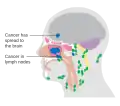

Cancer

Carcinoma of the maxillary sinus may invade the palate and cause dental pain. It may also block the nasolacrimal duct. Spread of the tumor into the orbit causes proptosis.[1]

Maxillary sinus cancer that has spread to the brain

Maxillary sinus cancer that has spread to the lymph nodes